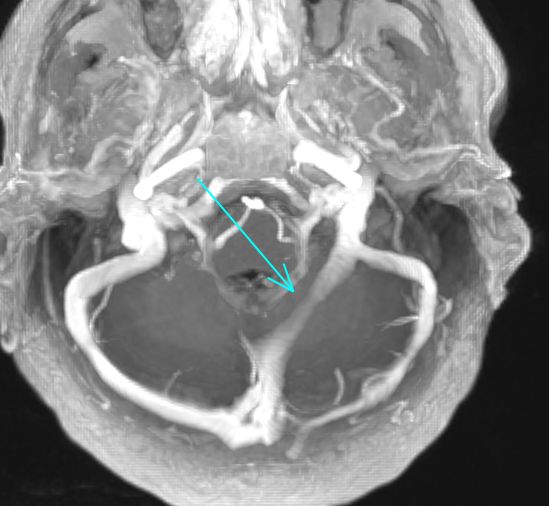

Dilated internal vertebral venous plexus

(due to low CSF pressure from overshunting)